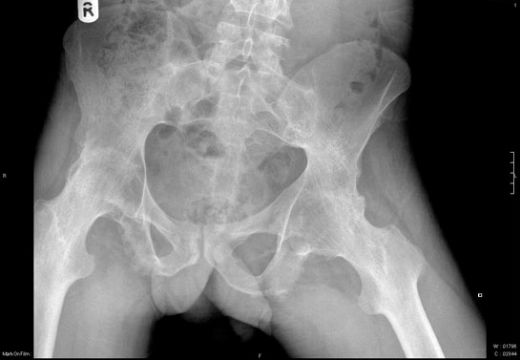

Tanı Yöntemleri Kalça kemiği ödeminin tanısı, klinik değerlendirme ve çeşitli görüntüleme teknikleri ile konulmaktadır. Bu süreçte: